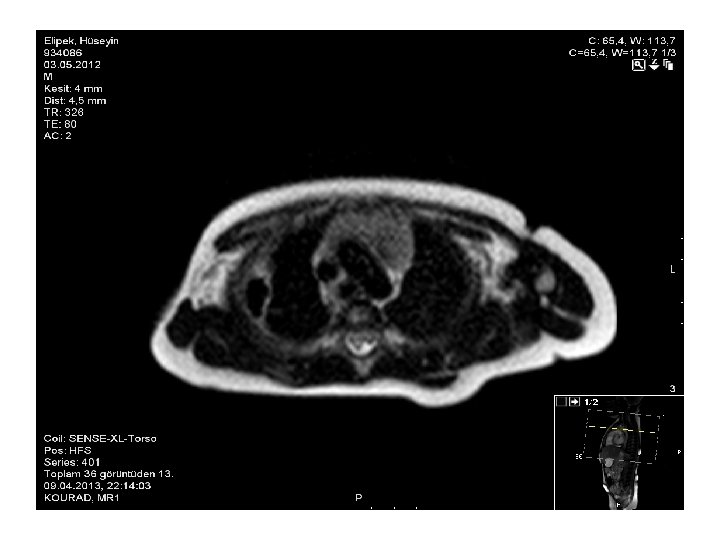

09/04/2013 Tarihli Toraks MR • Akciğer parankim alanlarının değerlendirilmesinde; aktif infiltratif görünüm ve nodüler lezyon saptanmadı. • Sağ akciğer alt lobda 9 x 14 mm boyutlu abse ile uyumlu içerisinde hava bulunan kalın duvarlı ve duvarı kontrast tutan kitle lezyon izlenmektedir. • Hastanın 26/03/2013 tarihli toraks BT incelemesine göre boyutları küçülmüştür. • Ayrıca sağdaki plevral efüzyon gerilemiştir. • Sağ akciğer alt lob posteriorda hafif konsolide görünüm izlenmekte olup, 26/03/2013 tarihli incelemeye göre gerilemiştir.

24/04/2013 Tarihli Toraks MR • 09. 04. 2013 tarihli MR incelemede sağ akciğer alt lobda izlenen kalın duvarlı abse ile uyumlu lezyon günümüz MR incelemesinde belirgin derecede küçülmüş olup çapı 1 cm ölçüldü. • Sağda bu alan komşuluğunda plevrada fokal kalınlaşma ve minimal plevral efüzyon izlenmektedir. • Sağ akciğer alt lob posteriorda hafif konsolide görünüm izlenmekte olup, 26/03/2013 tarihli incelemeye göre gerilemiştir.